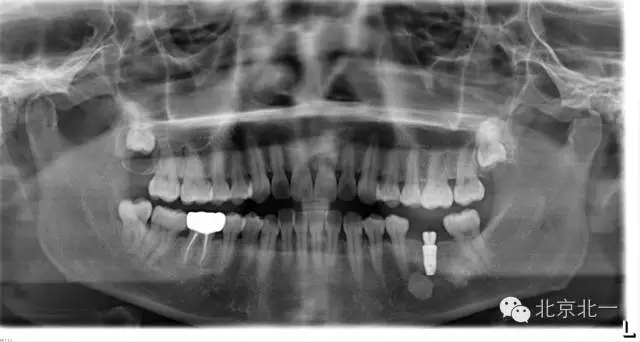

先看一例病例。頜骨內(nèi)單發(fā)高密度影像。是什么?能不能影響種植, 骨島是什么鬼?需要怎么處理?

如已經(jīng)證實骨島,是可以進行種植牙。但是骨島和致密性骨炎不好區(qū)別。 因為致密性骨炎如果進行種植必將失敗,切記!切記!切記!

總結:出絕招,如果遇到診斷不明確的骨島或者高密度影像, 最好的方式就是躲避, 不碰及它。

【口腔種植】致密性骨炎/牙骨質(zhì)增生/骨島如何鑒別?

頜骨三種高密度影像的鑒別

3)骨島:

概述:

主要和根尖型骨島鑒別,主要集中位于根尖區(qū)的骨島,

【CBCT表現(xiàn)】:

在CBCT上,根尖型骨島無低密度帶狀影包繞,與周圍骨質(zhì)分界清晰,具有特征性的毛刷樣邊緣,且其發(fā)生區(qū)域的牙根牙周膜影像連續(xù)、完整、不導致頜骨的膨隆。

右下頜C4根尖區(qū)課件一類圓形高密度影,與周圍骨質(zhì)分界清晰,C4牙周膜影像連續(xù)、完整,下頜骨未見膨隆。